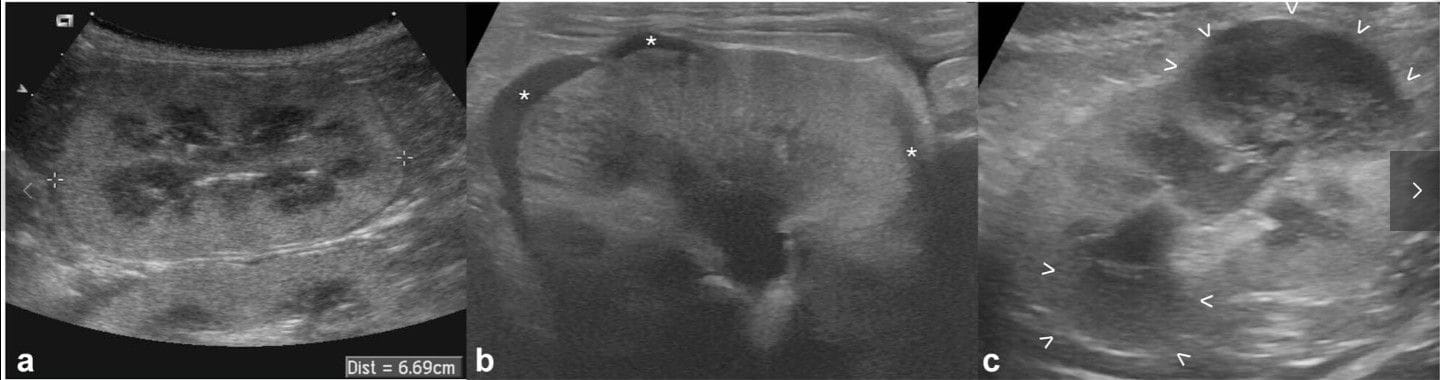

Ultrasonographic appearance of confirmed renal lymphoma at diagnosis (T0) in three cats: (a) marked nephromegaly: the caliper is measuring the renal length at 66.9 mm (range of normality is up to 44 mm); (b) hypoechoic subcapsular rim: crescent-shaped hypoechoic subcapsular thickening is seen in multiple portions of the kidney (*); and (c) renal nodules/masses: two well-defined, hypoechoic masses are visible at the cranial and caudal poles (between arrowheads)